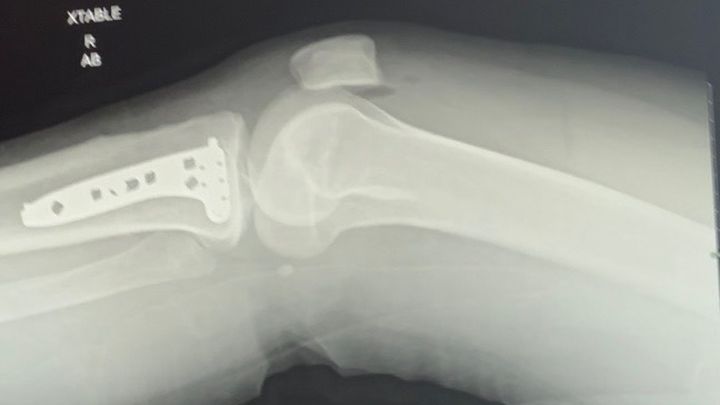

Devin is a month out from surgery and is tackling healing head-on just like she does life. She has learned how to get around her house by scooting herself backwards in her office chair with the walker on her lap, getting groceries delivered and carrying the bags in on a broom handle, and keeping herself entertained with her artistic expression. She is in a new brace; however, she is still having some blood flow/circulation issues they are monitoring.